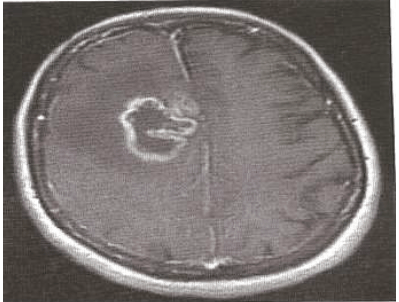

Paciente, sexo masculino, realizou uma ressonância magnética de encéfalo, mostrada na figura abaixo, e o exame histopatológico demonstra neoplasia glial com necrose e hiperplasia endotelial.

RM axial ponderada em T1 pôs-contraste.

Qual das opções abaixo de tratamento serão potencialmente benéficas?